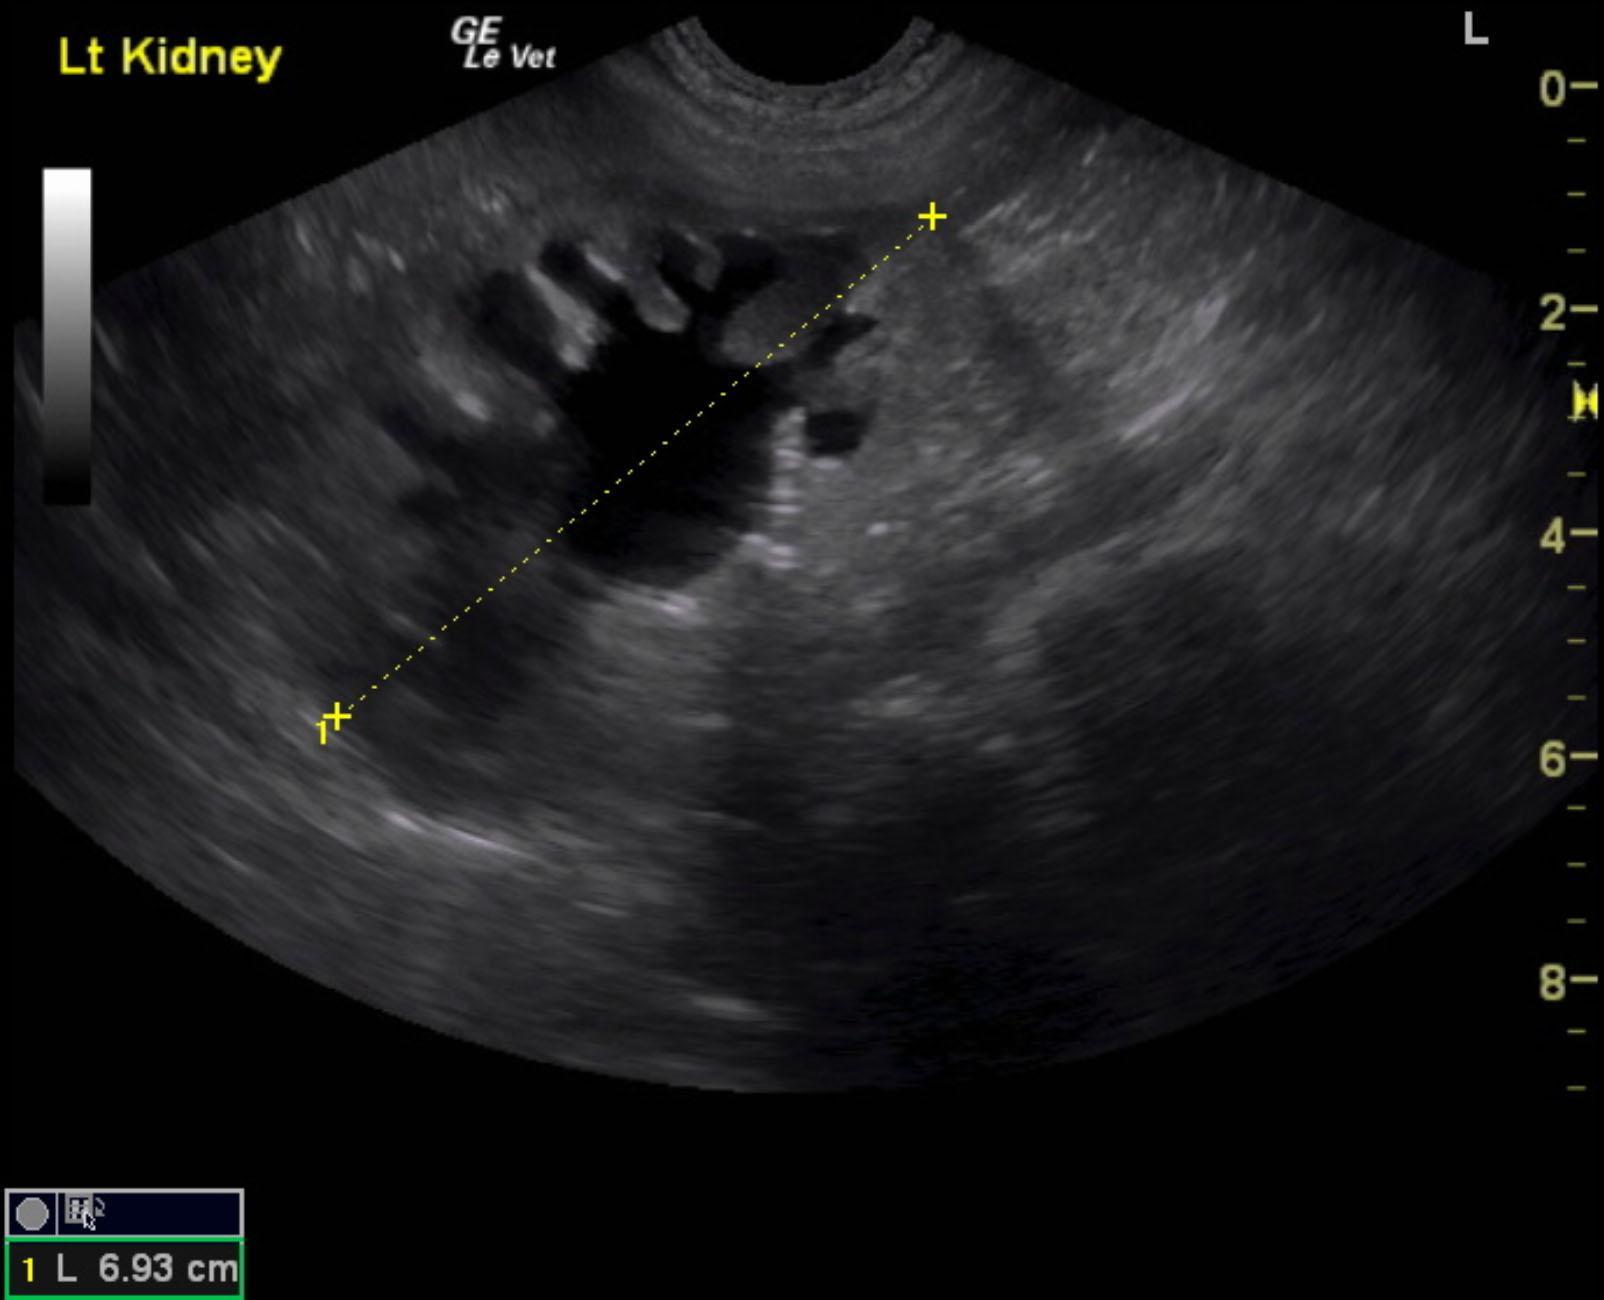

A 1-year-old neutered male Labrador retriever dog was presented for evaluation of urinary incontinence. Urine specific gravity was 1.039, and bloodwork was within reference range.